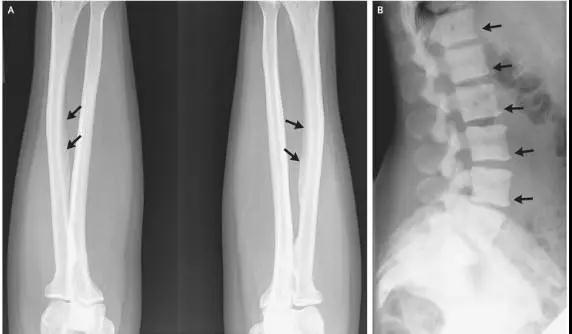

儿童因饮用水含氟量过高而导致氟中毒,他们出现关节僵硬、骨骼变形、下肢弯曲等症状,牙齿呈黄褐色或黑褐色斑纹。据悉,约有1000人因氟中毒而残疾。

如果饮水中的氟化物更高时,例如每升水中含氟化物3-4毫克或以上时,则将有相当一部分成人会患氟骨症。这是一种十分痛苦的骨病,这些病人行动不便,有的甚至丧失劳动能力,生活不能自理。